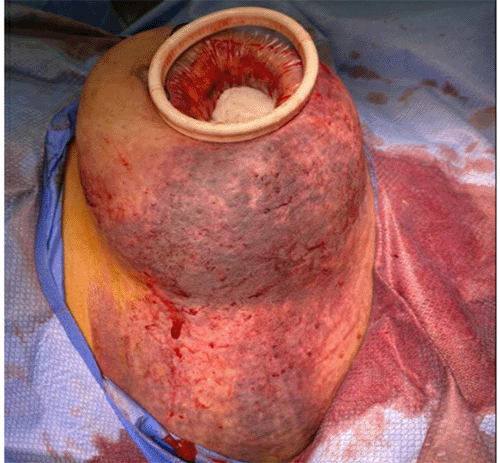

Despite initial closure and compression bra application, postoperative bleeding led to hypotension and required transfusion of two units of packed red blood cells. Refractory hemorrhage necessitated 4F-PCC for rivaroxaban reversal.1 A second surgery followed shortly after, removing an additional 500 cc of clot. A wound protector facilitated visualization of deep breast tissues and chest wall (Figure 3). No further active bleeding was observed, and the hematoma cavity was left open with tight packing before surgical ICU admission for continued resuscitation.

Figure 3. Chest Wall Hematoma Exposed with Wound Protector for Optimal Visualization. Published with Permission